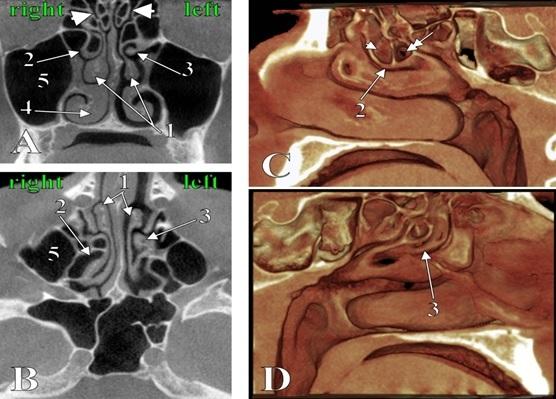

The nasal turbinates adhere to the lateral nasal wall and are subjected to various morphological variations. A common variation is concha bullosa, the pneumatization of a nasal turbinate. Another possible variation is the secondary middle turbinate (SMT) which originates from the lateral wall of the middle nasal meatus. Pneumatized SMTs were previously found only twice in Computed Tomography (CT) studies. It is hereby reported the third such evidence, gathered in a 44 y.o. male patient which was scanned in Cone Beam CT (CBCT) for routine dental medical procedures. In the present case the superior turbinates were pneumatized and were found bilateral SMTs. The left SMT was unpneumatized and projected medially and the right SMT was pneumatized and projected infero-medially. The right pneumatized SMT was communicating through a narrow isthmus with the ethmoidal bulla; beneath these two, a large ethmoidal infundibulum opened medially through a narrow semilunar hiatus. Such extremely rare anatomic variations could impede on the normal drainage of the ostiomeatal unit and could lead to inadvertent surgical corridors if they are not documented in CT or CBCT.

鼻甲附着于鼻腔外侧壁,形态多样。常见的变异是泡状鼻甲,即鼻甲的气化。另一种可能的变异是继发中鼻甲(SMT),它起源于中鼻道的外侧壁。气化的SMT以前在计算机断层扫描(CT)研究中仅发现过两次。在此报告第三次此类证据,该证据来自一名44岁男性患者,其因常规牙科医疗程序接受了锥形束CT(CBCT)扫描。在本病例中,上鼻甲气化,双侧发现SMT。左侧SMT未气化,向内突出;右侧SMT气化,向内下突出。右侧气化的SMT通过一个狭窄的峡部与筛泡相通;在这两者下方,一个大的筛漏斗通过一个狭窄的半月裂孔向内开口。这种极其罕见的解剖变异可能会阻碍窦口鼻道复合体的正常引流,如果在CT或CBCT中未记录,可能会导致意外的手术通道。